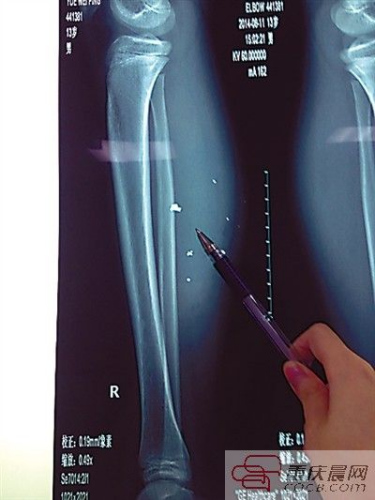

平平的小腿內異物清晰可見。

第二天,傷勢過重的平平轉院至兒童醫院,骨科醫生周悅航說,經檢查,平平右小腿腫脹明顯,發現有爆炸傷伴異物殘留,后側可見兩處1厘米裂口,傷口較深,約1.5-2厘米。通過X光片可見患兒右小腿皮下多處高密度影,即手機爆炸后進入小腿的異物,大約10處,需通過手術取出。